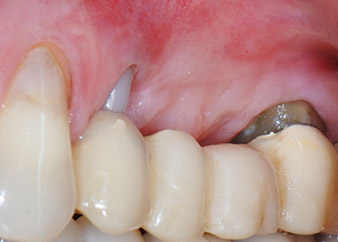

la raíz bucal de la pieza 24 mostraba una pérdida total del hueso y de la fijación

Fig. 2 y 3: Después de abrir los colgajos, un mes después de realizar la revisión endodóntica y de iniciar la terapia periodontal en toda la boca, la raíz bucal de la pieza 24 mostraba una pérdida total del hueso y de la fijación.

Un mes después, en el día de la intervención, el dolor y la inflamación se habían reducido al mínimo en la pieza 24, pero seguía habiendo una movilidad de clase II de Miller. Después de la apertura de los colgajos y de la limpieza del tejido infectado periapical y perirradicular, la extensión del defecto óseo quedó evidente (figuras 2 y 3).

En la raíz bucal, faltaba todo el hueso vestibular y distal. Básicamente, la fijación se limitó a la raíz palatal, lo que corroboró el mal pronóstico preliminar. La pieza 27 también mostró una fijación horizontal reducida (figura 12) y una rarefacción apical mínima (figura 1), si bien sin síntomas clínicos.